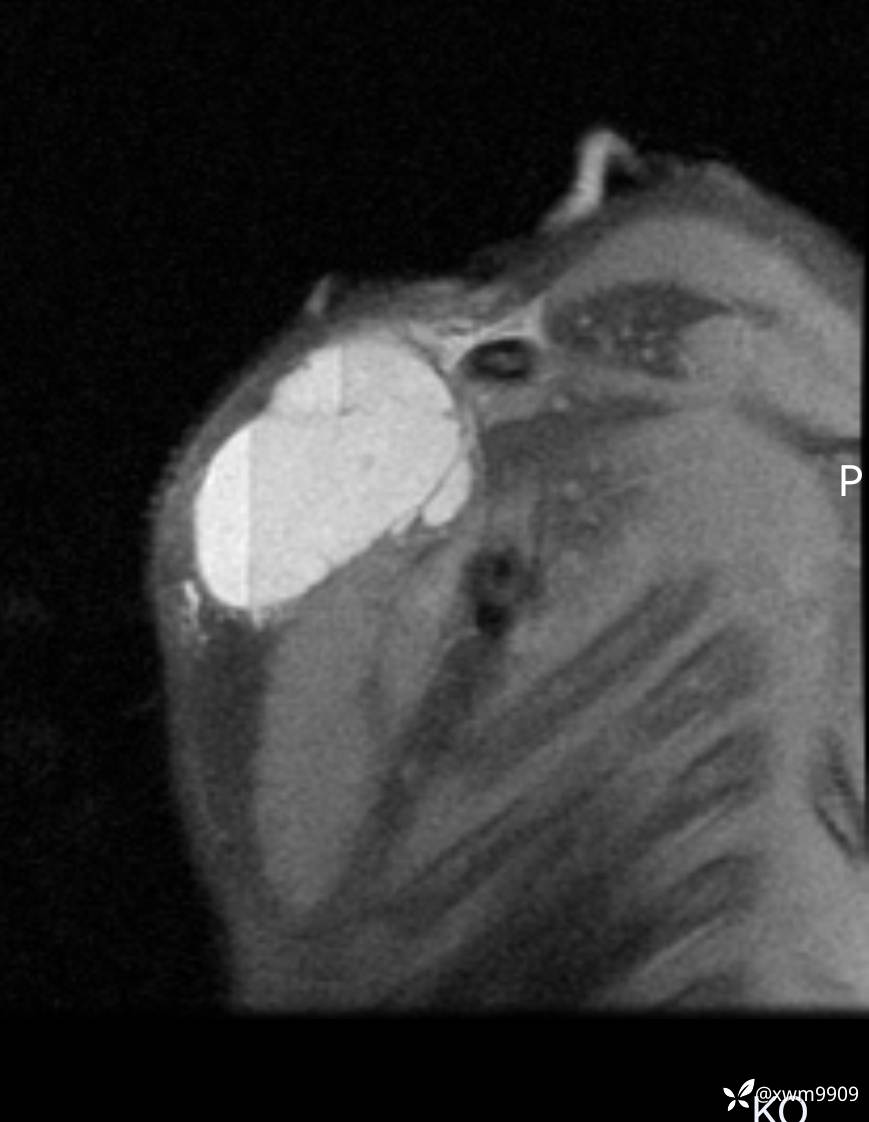

2024-03-19,门诊“摔伤右锁骨肿胀疼痛6小时。拟“锁骨骨折”要求摄:右肩关节正侧位,右锁骨轴位检查。

2024-03-20,女,6岁。因“发现右侧胸部肿物伴疼痛1天”入院。

2、现病史:家属代诉昨日洗澡时发现右胸肿物,压痛明显,查DR:未见明显异常,自行予云南白药,症状稍好转。临床拟:锁骨周围血肿收入院。

3、查体,右锁下方可及一约5x6Cm肿物,软丶边清丶未见明显发红,肤温不高,压痛明显,不可推动,稍有波动感。其他无特殊。

CT: